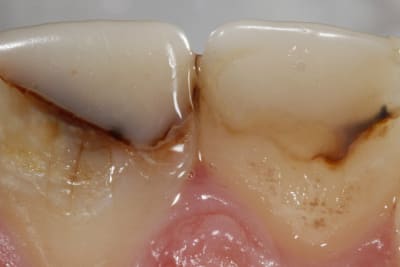

1/ Préop

2/ A 6 jours avec rebasage des provisoires au composite (un peu cracra)

3/ A 3 semaines avec deuxième jeu de provisoire